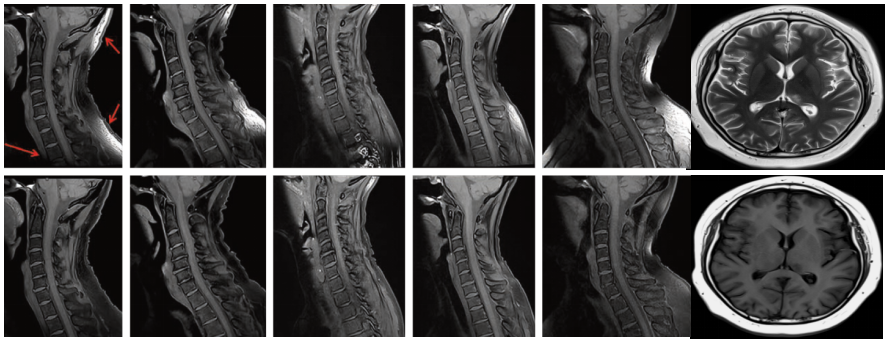

核磁共振扫描,人体脊椎